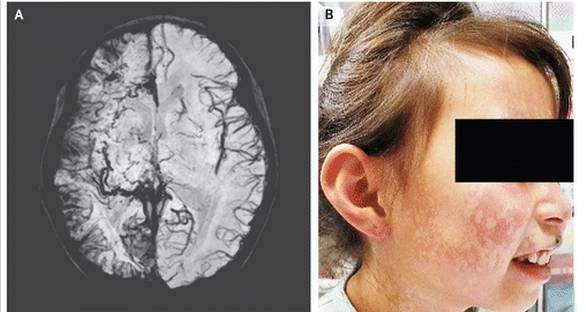

第一例讲的是斯特奇-韦伯综合征(Sturge-Weber),又称为脑-面血管瘤病,以发现此病的两位英国医生的名字而命名。本病与近亲结婚造成遗传性致病因素有关。这一例是典型的少见病的典型临床表现。